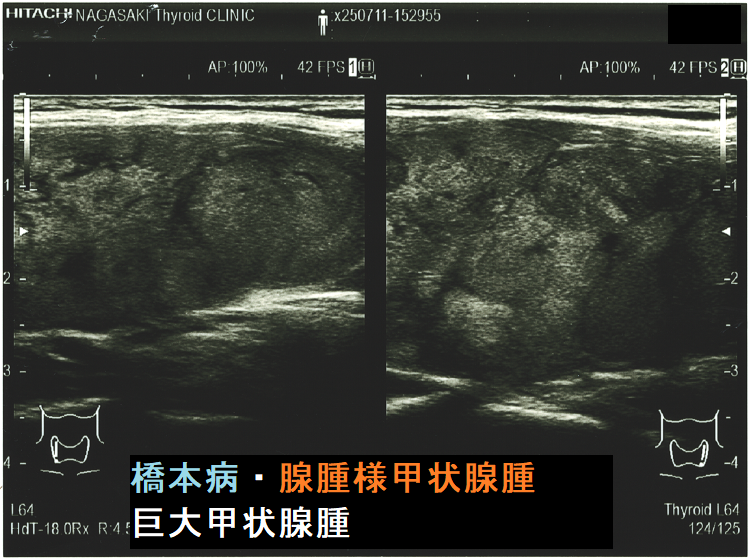

ケース⑤ 橋本病を基盤とする腺腫様甲状腺腫・巨大甲状腺腫(気管・食道圧排)